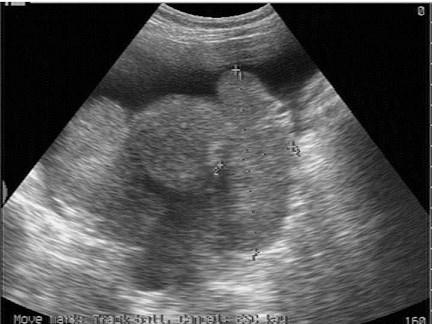

问题 女性,39岁,胃癌术后。妇科检查:两附件区触及包块。超声检查如图,最可能的诊断为?(?)

选项 A.囊腺癌 B.囊腺瘤 C.黄体囊肿 D.转移性卵巢癌 E.无性细胞瘤

答案 D